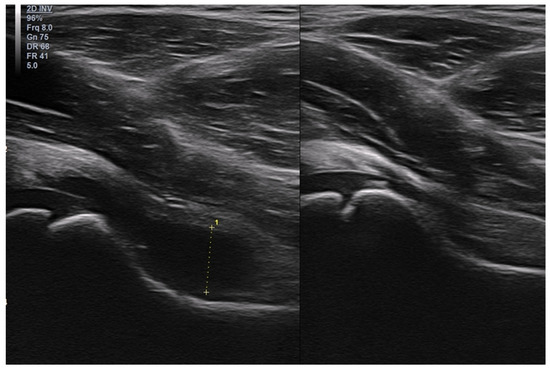

Basic Differences and Most Common Findings in Ultrasound Examinations of Musculoskeletal System in Children: A Narrative Literature Review

We present basic differences in the musculoskeletal ultrasound examinations between adults and children. Examiners who deal with adults on a daily basis have shared concerns about examining children. Such concerns may arise from the different approach to child ultrasounds, but they also come [...] Read more.

We present basic differences in the musculoskeletal ultrasound examinations between adults and children. Examiners who deal with adults on a daily basis have shared concerns about examining children. Such concerns may arise from the different approach to child ultrasounds, but they also come from differences in anatomical characteristics according to developmental age. We discuss the presence of growth plates, as well as non-mineralized parts of the bones. We also refer to the pathologies most often found in ultrasounds in early developmental stages. In the PubMed database, the set of keywords: “msk ultrasound in children”, “pediatric msk sonoanatomy”, “coxitis fugax”, “pediatric Baker’s cyst”, “Baker’s cyst ultrasonography”, “bone septic necrosis in ultrasonography”, “ultrasonography in juvenile idiopathic arthritis”, and “ultrasonography in juvenile spondyloarthropathies”, was used to identify a total of 1657 results, from which 54 was selected to be included in the article. We discuss the problem of osteochondritis dissecans, Osgood-Schlatter disease, examples of ligament injuries (especially in relation to the knee and ankle joints), exfoliation of growth cartilages, osteochondroma, exudates and inflammations affecting joints, and Baker’s cysts. In this way, we have collected useful information about the most common diseases of the musculoskeletal system in children. Full article

Show Figures

Figure 1